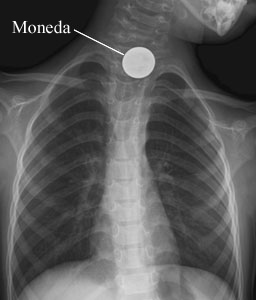

La vista anterior de la radiografía de pecho (tórax) de un niño muestra una moneda tragada.

Cortesía de Intermountain Medical Imaging, Boise, Idaho. Todos los derechos reservados.